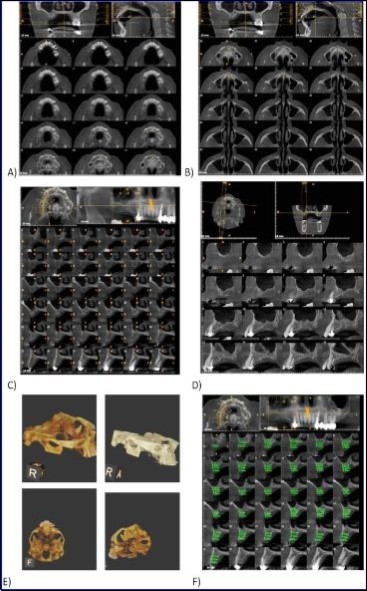

Sinus augmentation procedures were carried-out in 17 patients seeking implant options for oral rehabilitation including 10 for direct and 10 of indirect procedures (n=20, 10 direct and 10 indirect). The study comprised of 43% females and 57% males with a mean age of 46.07 years. A total of 17 patients (20 segments) satisfying the above criteria requiring placement of implants in atrophic maxilla/ increased pneumatisation of the maxillary sinus were selected for the study. The patients were informed about the study including the use of the synthetic graft material and their approval was sought before their inclusion in the study. A written informed consent was obtained from each of the participating patients. For each patient, a detailed case history was taken including chief complaint, history of presenting illness and medical history and personal history. A thorough clinical examination, including systemic and regional examination, was done. Patients with sinus pathology, previous sinus surgeries, chronic smokers, patients under 18 years of age, and with underlying systemic conditions which contradicts any surgical procedures were excluded from the study. The type of sinus lift was decided based on the pre-operative residual bone height evaluated radiographically. The residual bone height was recorded using CBCT scan and a computer based software where the measurements were made from the crest of the ridge till the sinus floor lining. Indirect sinus augmentation was done in patients with a bone height of <9mm but more than or equal to 5mm. Patients with a bone height of less than 5mm were taken up for direct sinus augmentation. The period of edentulousness varied from 6 months to 12 months. Apically tapered, commercially pure titanium implants (Life Care Devices Private Limited Mahim, West Mumbai, India) were used for patients undergoing indirect sinus augmentation. The length of implant was 8, 10, and 11.5 with diameters of 3.5, 4.0, and 5 mm respectively. Patients in the category of direct augmentation underwent the lateral approach procedure and augmentation with an alloplastic graft material. Implant placement was done after 6 months as the second stage procedure. The patients were assessed clinically at immediate post-operatively, and at 1 week, 1 month, 3 months, and 6 months post-operatively. Radiographic assessment for bone height was done pre-operatively and at 6 months post-operatively using cone beam computer tomography. In this comparative study, the measurements were tabulated and statistically analyzed to evaluate the difference in increase in bone height between direct and indirect sinus augmentation procedures radiographically. Orthopantomographs (screening tool) were taken to rule-out other pathologies and as a part of initial assessment. CBCT scans were assessed for pre-operative and post-operative bone height, bone width and bone density. The CBCT scans were obtained from Kodak 9300 which is a hybrid machine using a CS3D imaging software and flap panel detector sensor with exposure parameters of 90 KVp and 10 mA and resolution of 90 microns. The cross sections were made 1mm apart. (Image 1, Image 2, Image 3) The bone height measured pre-operatively using CBCT considered the pre-operative bone height as a measurement taken from the crest of the ridge till the sinus floor and post-operatively, from the crest till hyper-density evident apically. These measurements were standardized as a computer software drawing tool was used. Bone width was taken as the bucco-palatal width at three intervals- at the crest, 3mm from the crest and 6mm from the crest. Bone density was assessed visually by the width of trabecular pattern and were classified based on Misch‘s classification.4 Another additional bone density tool used was the pixel values (the gray scale values) obtained on the CBCT scan, although not reliable, and comparison done pre-operatively and post-operatively. The pixel values contained were a mean of three measurements obtained along the residual bone corresponding with the bone width levels.

Image 1.Routine sequential CBCT scans A and B) Axial sections; C) Cross section; D) Oblique sagittal section; E) 3-D reconstruction; F) Width measurement